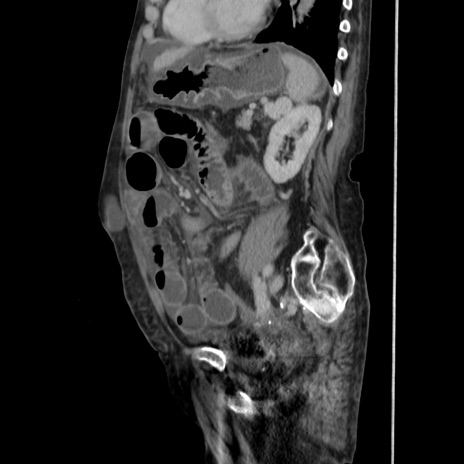

横断像

【症例】80歳代 女性

【主訴】腹部膨満感

【現病歴】他院にて肝硬変にてフォロー中。1週間前から便秘、腹部膨満感、臍部腫瘤あり受診となる。

【既往歴】肝硬変

【身体所見】腹部膨隆あり、皮膚変化なし、疼痛なし。

【データ】WBC 4600、CRP 0.25